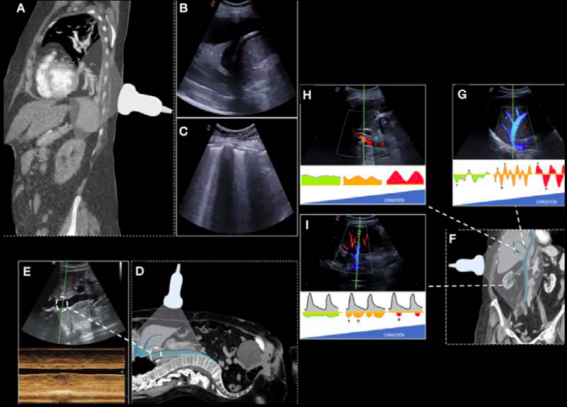

How to assess systemic venous congestion with ?? Evaluation of

🖥 IVC

🖥 hepatic veins

🖥 portal vein

🖥 renal vessels

technique, interpretation & pitfalls, and score

Open access @EchoSoliman@twitter.com

📖 bit.ly/3YS8Dzt

Open access

How-to assess systemic venous congestion with published today at @ESC_Journals

A pleasure to collaborate with the legend @Ad12Andre

academic.oup.com/ehjcimaging/a